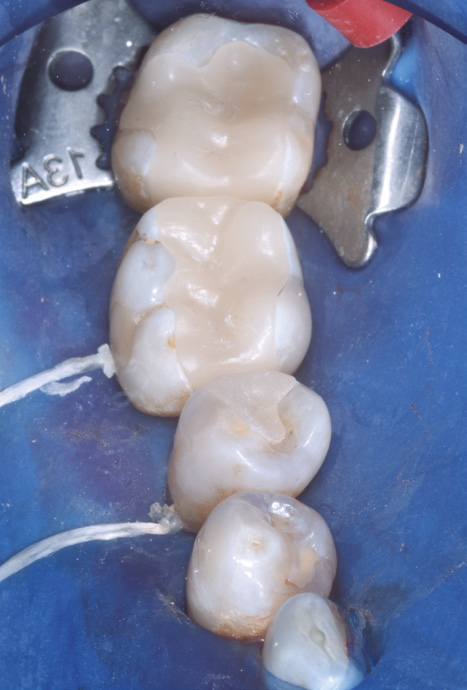

Close-up of dental procedure showing a curing light hardening resin on teeth, surrounded by a blue dental dam. The setting appears clinical and focused.

Final light-cure with 3M™ Elipar™ DeepCure LED Curing Light after excess clean-up.

Close-up view of the lower row of healthy molars inside a mouth, showing clean and smooth surfaces, surrounded by pink gums.

Final situation.